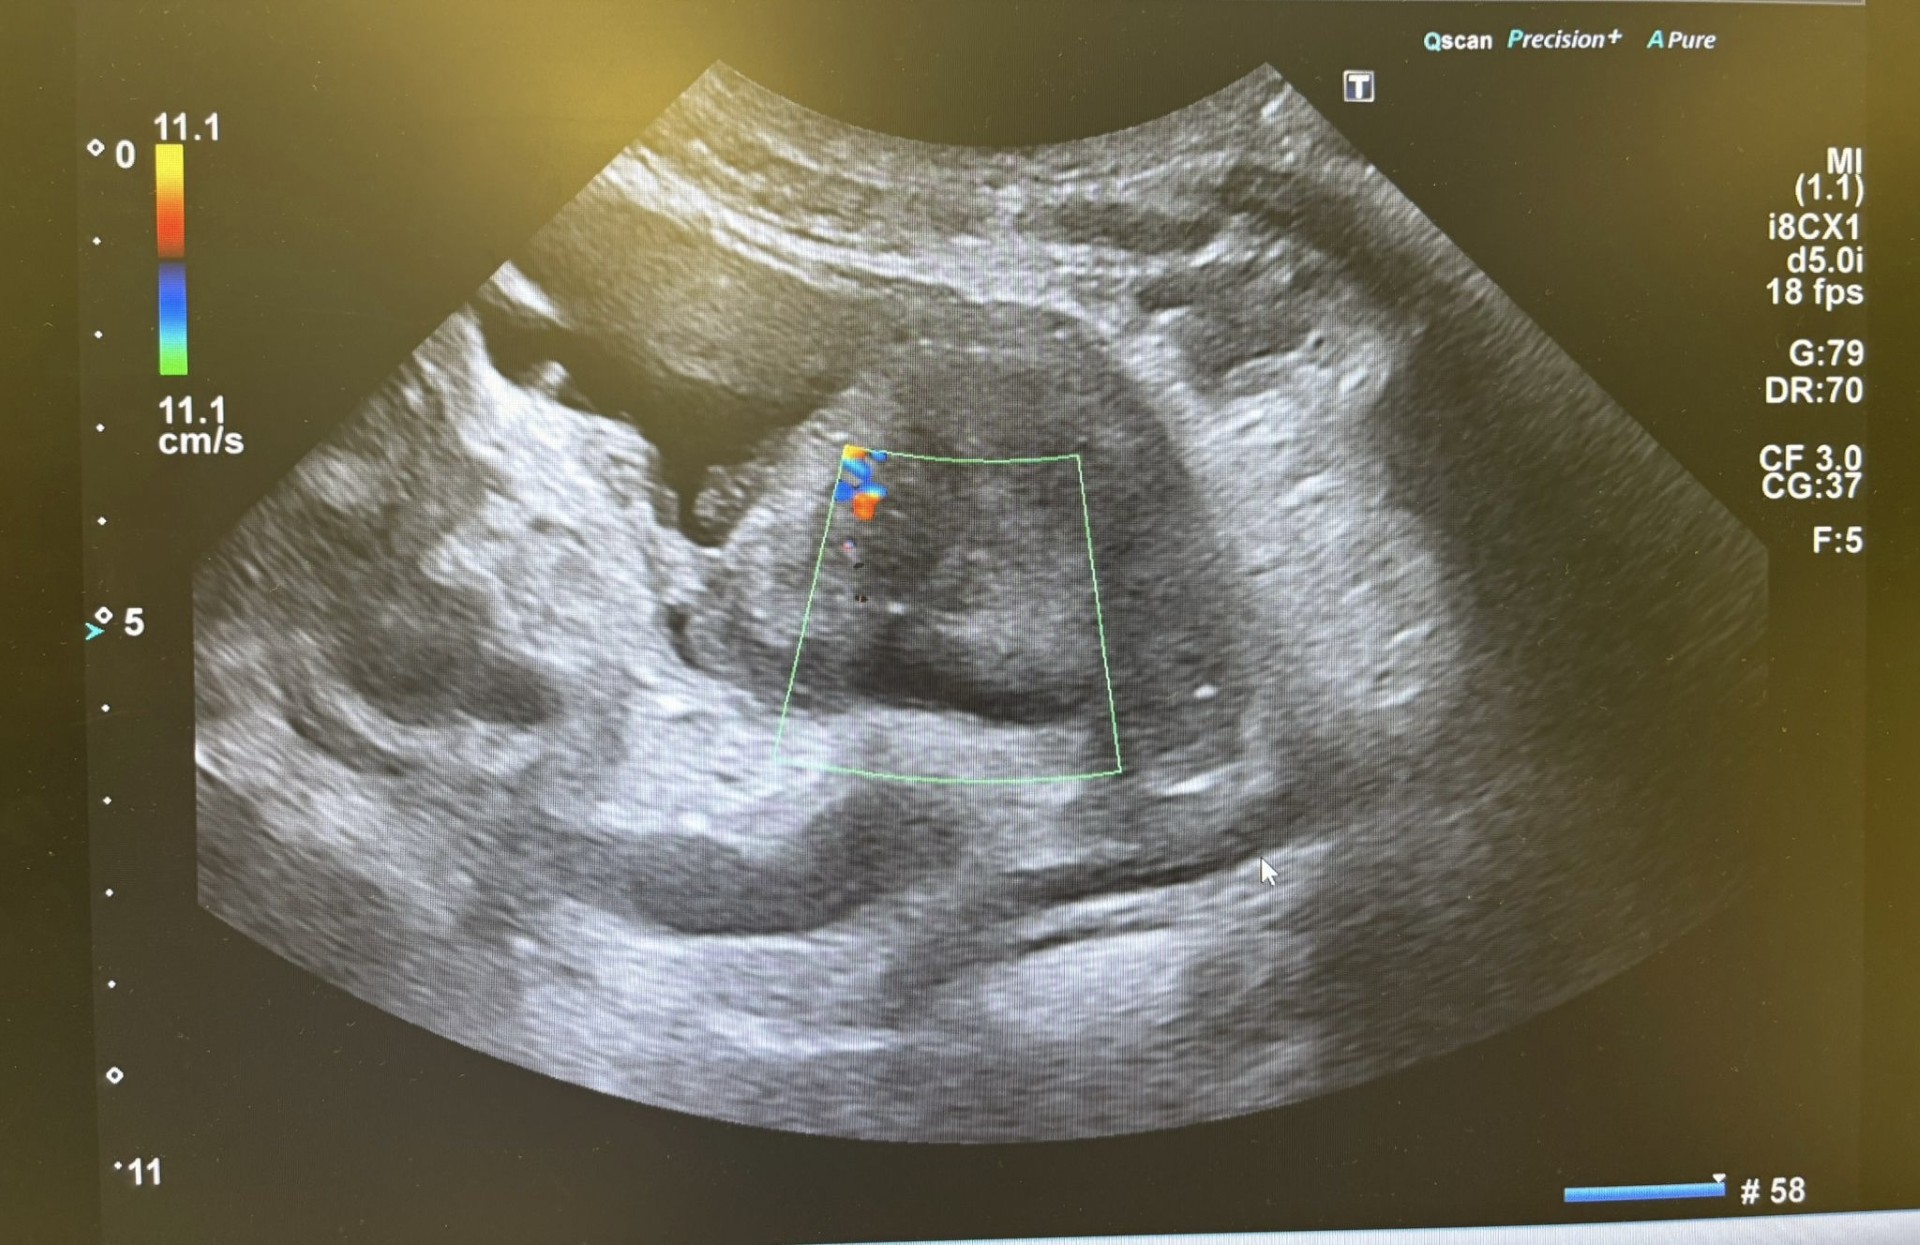

Presentamos el caso de un varón de 62 años fumador crónico (40 paquetes/año) que consulta por síndrome miccional sin fiebre de 20 días de evolución, caracterizado por tenesmo vesical, polaquiuria y hematuria. Había sido tratado previamente con cefixima sin mejoría clínica. En atención primaria se aisló Staphylococcus haemolyticus resistente a meticilina en urocultivo, por lo que fue derivado a urgencias. A su llegada se encontraba afebril y normotenso, con leve dolor abdominal a la palpación y retención urinaria. La analítica mostró leucocitosis (10.720/mm³), neutrofilia y elevación de PCR. El sedimento urinario reveló leucocituria, hematuria y bacteriuria. Ante la persistencia de síntomas y la presencia de retención urinaria se realiza ecografía vesicoprostática en Urgencias objetivándose masa sólida intravesical, irregular con base ancha y vascularización aumentada en Doppler, sugestiva de neoplasia vesical.

Derivación preferente a Urología con informe y registro de imágenes ecográficas.

Se realizó una resección transuretral. El informe operatorio describe una masa vesical que ocupa todo el trígono y parte de la cara lateral derecha, claramente infiltrante. Se solicitó TAC toracoabdominal y pélvico para estudio de extensión.